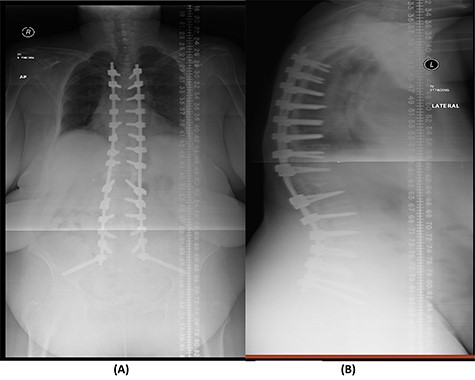

Over a year after the surgical procedure with the bridging technique, the patient presented with a new-onset lower back pain after hearing a crack. X-ray showed bilateral rod fractures and the CT scan showed re-ossification of the involved levels (T11–L3; Fig. 5). An MRI showed complete recovery of the infection without cord compression (Fig. 6). At this stage, we elected to proceed with a revised surgical intervention that involved adding bilateral pedicle screws at the re-ossified vertebrae (T11, T12, L2 and L3). The patient tolerated the surgery well and had a normal neurological examination postoperatively. CT scan post revision demonstrated fixation of T5 to S2 alar-iliac with a well-fixed construct. CRP level upon discharge was 7 mg/l and procalcitonin was <0.02 ng/ml. The patient was recovering well at follow up 1 year later (Fig. 7).

(A) AP lumbar spine X-ray demonstrating final fixation from T5-S2-alar-iliac screws. (B) Lateral spine X-ray.

The patient underwent a revised form of posterior spinal fixation from T5 to S2 using a bridging technique and double rods on each side to allow healing and re-ossification of the vertebra with removal of the screws in T11–L3. Due to the instability of the bridging technique, the rods were broken and posterior fixation was deemed a failure. The patient underwent a revision of fixation with insertion of pedicle screws in all levels and a single rod on each side (Fig. 7). In this stage, complete eradication of the infection was achieved and there was no collection.